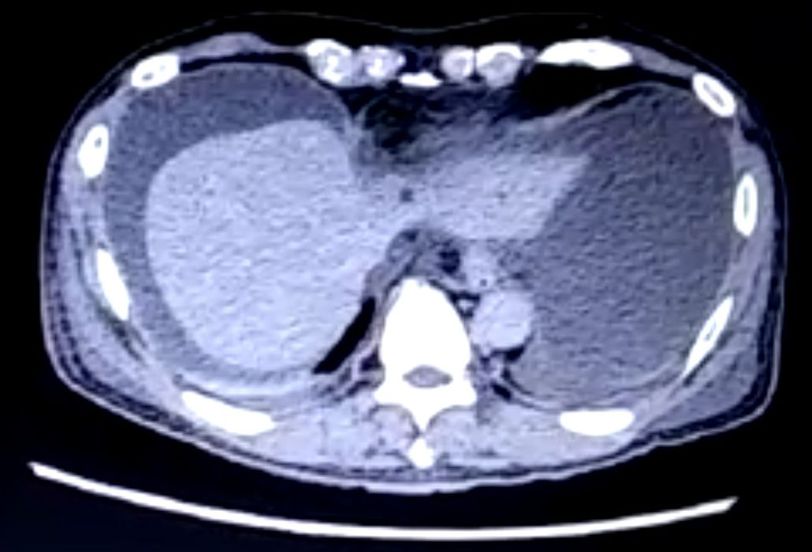

Liver CT scan

Male patient, 62 years old with hep B infection, what's the interpretation of this CT scan?